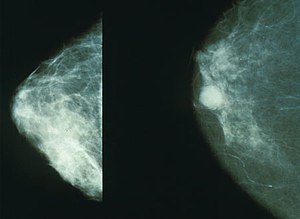

계적으로 여성은 3명 중 1명이 암에 걸린다고 합니다. 여성암 중 갑상선암 다음으로 두 번째로 높은 암이 유방암이라고 하는데, 중년 여성의 암 사망률로는 유방암이 1위라고 합니다. 유방암이란 유방에 나타나는 모든 악성 종양을 통틀어 말하는 것으로 보입니다. 유방암은 유방에 비정상적인 조직이 계속 자라거나 다른 장기에 퍼지는 위험한 병이라고 할 수 있습니다.